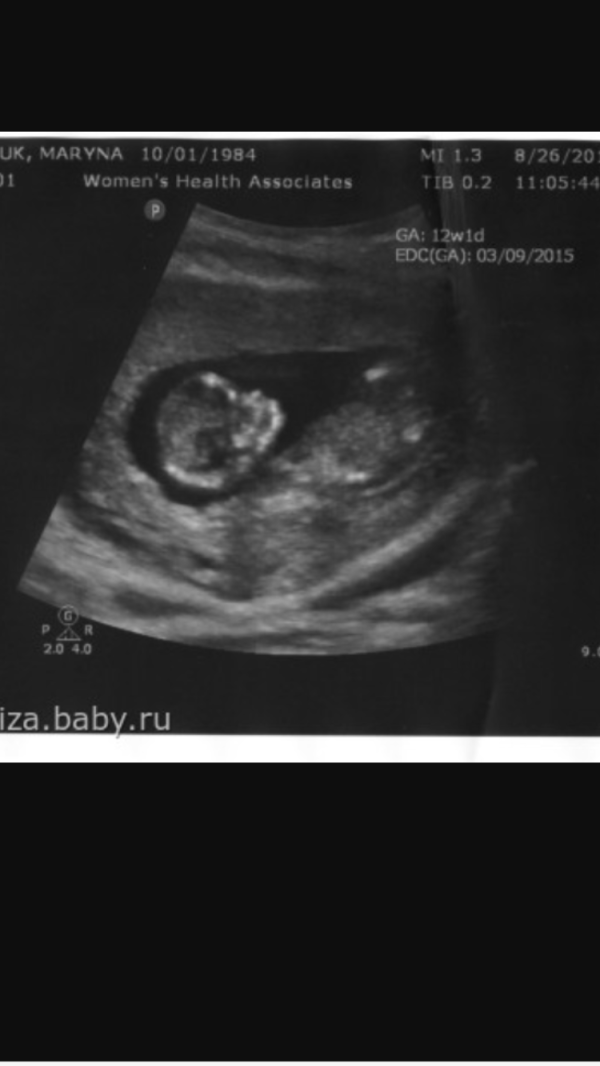

Первый скрининг такой трогательный !!! И так классно когда говорят что все хорошо!!! Тоже боялась , теперь на второй пойду смело)))